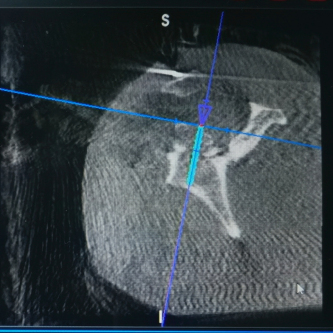

(术后影像)

近日,创伤外科中心A区张立峰教授团队成功完成91直播 首例也是自治区首例“天玑”II骨科手术机器人导航下精确定位经皮内固定肩关节盂骨折,在机器人的帮助下做到了最佳置钉角度和最佳置钉位置,本次手术减小了患者手术切口,且缩短了手术时间,同时缩短了骨科医生在X线下辐射时间。本例手术的成功实施,标志91直播 创伤外科骨科机器人导航下微创手术治疗达到国内先进水平。

“天玑”Ⅱ骨科手术机器人用于辅助医生精确定位植入物或手术器械,可广泛应用于骨科手术,其临床精度可达1mm以内。自2021年91直播 成功引进后,已完成各类骨科手术。本次应用骨科机器人进行肩关节盂骨折手术治疗,进一步拓展了“天玑”II骨科机器人的诊疗范围,完美呈现了“人机结合”,更为创伤急救中心的创新治疗带来新思路。创伤外科中心将继续充分利用骨科机器人的技术优势在新的领域开展临床治疗,提高自治区创伤救治水平,更好地造福患者。